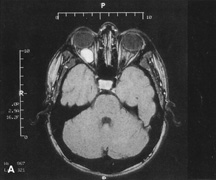

HISTORY AND PHYSICAL EXAMINATION A wide range of signs and symptoms may alert the ophthalmologist to involvement of the orbit by a pathologic process. These include proptosis or globe displacement; compressive optic neuropathy with visual field or visual acuity loss; refractive changes such as progressive hyperopia, restricted eye movements, and diplopia; optic disc changes, including pallor or edema; and fundus changes such as choroidal folds. These manifestations may be the consequences of a primary intraorbital disease or may occur secondary to involvement of the orbit by a process extending from the overlying soft tissues, periorbital sinuses, or intracranial cavity. All patients with suspected orbital pathology should have a thorough ophthalmic history and physical examination. Detailed questioning about the nature, onset, and progression of the chief complaint is necessary to formulate a differential diagnosis. Previous ocular and general medical history related to diseases, operations, medications, and family history should be obtained. A general review of systems will identify risk factors for related systemic diseases, such as hyperthyroidism, metastatic cancer, or lymphoma. A complete examination of the eye and periocular tissues is essential. Abnormal protrusion or displacement of the globe, extraocular motility disturbances, soft-tissue changes, and decreased corneal or periorbital cutaneous sensation should be specifically sought. Special attention always should be directed to evaluation of optic nerve function. Visual acuity testing alone is not sufficient because visual acuity often is preserved initially in patients with compressive optic neuropathy. All patients should be examined closely for detection of an afferent pupillary defect, abnormal color vision, or loss of contrast sensitivity. Formal perimetry should be performed to rule out peripheral field loss. If the presentation has been gradual, evaluation of old photographs may help establish the time course of the pathologic process. In selected cases, appropriate blood work to help identify orbital inflammatory or neoplastic processes also should be obtained. ORBITAL IMAGING Valuable information about the nature and extent of an orbital pathologic process is provided by imaging studies such as computed tomography (CT) scan, magnetic resonance imaging (MRI), and orbital echography. Better spatial resolution, ready accessibility, and lower cost make CT the preferred choice for orbital imaging in most cases. Orbital fat provides a natural contrast between most adjacent orbital structures on CT scanning, and orbital bones are visualized well. Computed tomography is essential for evaluation of the orbital bones because they cannot be imaged with MRI. Direct coronal or sagittal images are important to identify the relationship of a lesion to the optic nerve so that the surgical approach can be planned to avoid traversing the optic nerve (Fig. 1). Newer multislice helical CT scanners allow continuous acquisition of data so that a single rapid pass allows formatting in axial, coronal, and sagittal planes. Multislice CT provides shorter examination times with reduced motion artifact and radiation exposure when compared with conventional CT. Magnetic resonance imaging is useful in selected cases, especially when evaluating the orbital cranial junction. Significant bony artifact and a lack of orbital fat in the orbital apex make CT scan resolution of the orbital apex structures poor. Because cortical bone has low signal on MRI, there is no bone artifact when viewing the orbital apex on MRI. The lack of intervening fat in the apex to provide contrast is overcome on MRI because contrast is provided by the individual nuclear characteristics of each tissue so that the orbital apex structures are visualized well. Consequently, conditions that affect the optic nerve and chiasm, such as optic nerve meningioma and glioma, generally are evaluated with MRI rather than CT scan (Fig. 2). Use of a contrast agent such as gadolinium can further enhance the T1 signal intensity of lesions and is particularly helpful in imaging areas where there has been a breakdown in the blood–brain barrier. Because orbital fat produces a bright signal on T1-weighted images, orbital MR usually is performed with “fat suppression” to prevent masking of lesions. However, incomplete fat suppression can produce artifacts that may be misinterpreted as abnormal enhancement. A few other orbital conditions are better visualized with MRI than CT scanning.1–3 Often, organic foreign bodies, such as wood, are not imaged well with CT scan. These foreign bodies often are visible with MRI. However, care must be taken when imaging any metallic intraocular or intraorbital foreign body because the strong magnetic field of the MR scanner may cause the foreign body to shift position and damage surrounding structures. In some tumors and vascular anomalies, high blood flow is appreciated on MRI. This is caused by a lack of signal, known as a flow void, created by blood flowing rapidly through larger vessels. Tumors that originate in the brain and extend into the orbit secondarily, such as sphenoid wing meningioma, also are visualized well with MRI. However, bony detail and calcification within the meningioma are not imaged well. In unusual circumstances such as this, CT scan and MRI may prove to be complementary, and both techniques may be required to fully evaluate the orbital disease process. Orbital echography can provide useful information in the evaluation of orbital disorders. Because each tissue has its own acoustic characteristics, echography can provide a high degree of tissue contrast. Spatial resolution also is quite good. In some situations, echography can provide information not available on CT scan or MRI. These instances include detection and measurement of blood flow4 and intraoperative localization of small foreign bodies.5 Orbital echography requires specialized equipment and a large amount of expertise to obtain the detailed information that is readily available with CT scan or MRI; consequently, its use has decreased. Recent advances in orbital imaging have been summarized by Lee and colleagues.6 |